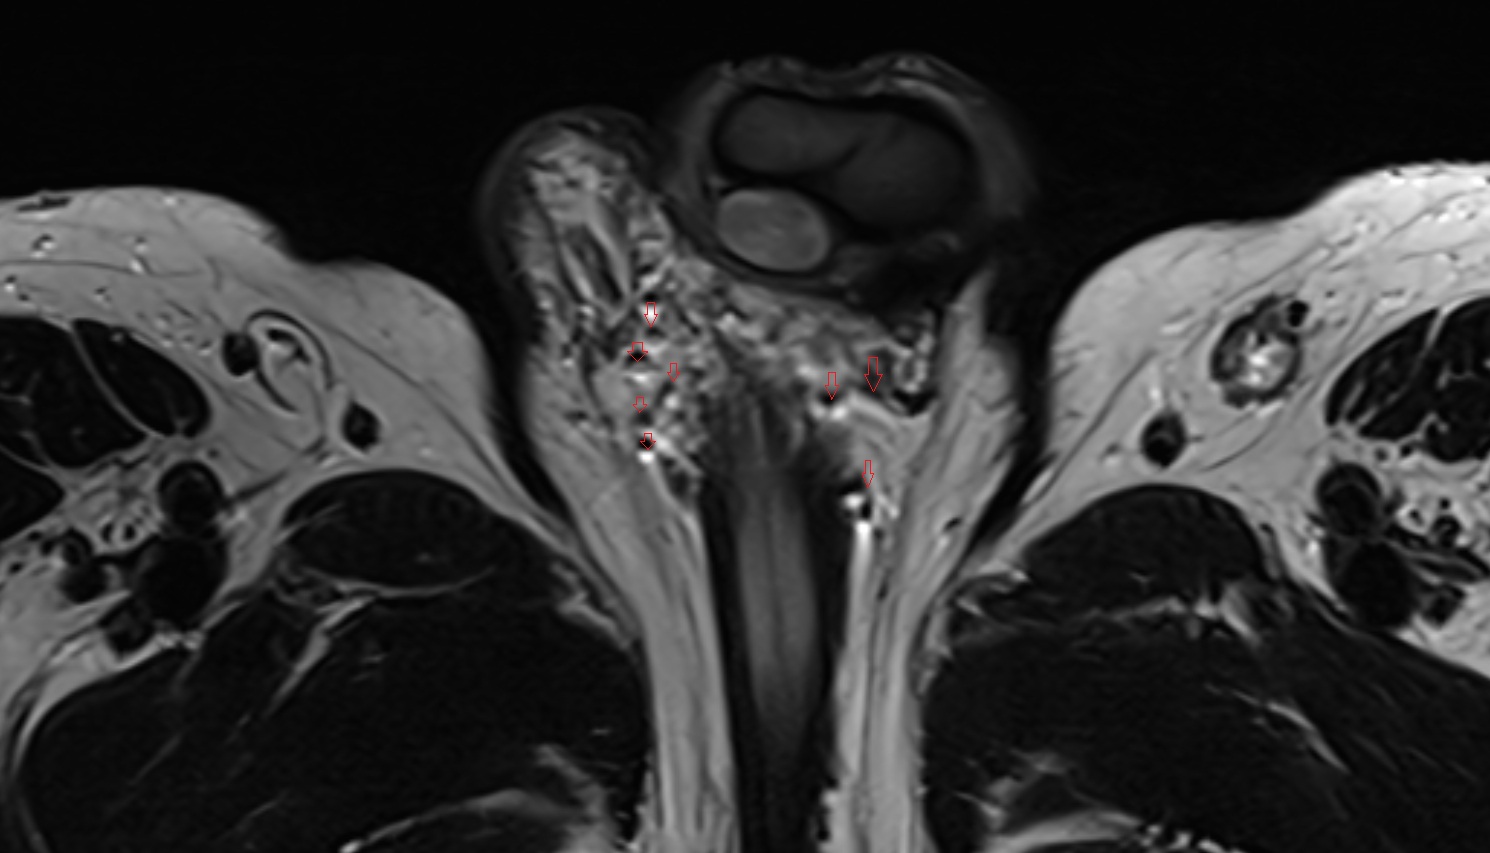

- Peripheral zone of prostate

- Anterior Fibromuscular Stroma of prostate

- Central zone of prostate

- Transitional zone of prostate